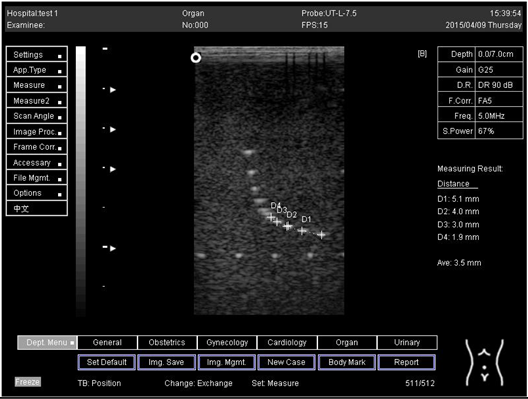

9.0 Axial resolution

Biomimetics 07 00130 i001

D1 = 4.9

D2 = 4.1

D3 = 3.1

D4 = 2.2

Lateral resolution

Biomimetics 07 00130 i002

D1 = 5.0

D2 = 4.0

D3 = 3.0